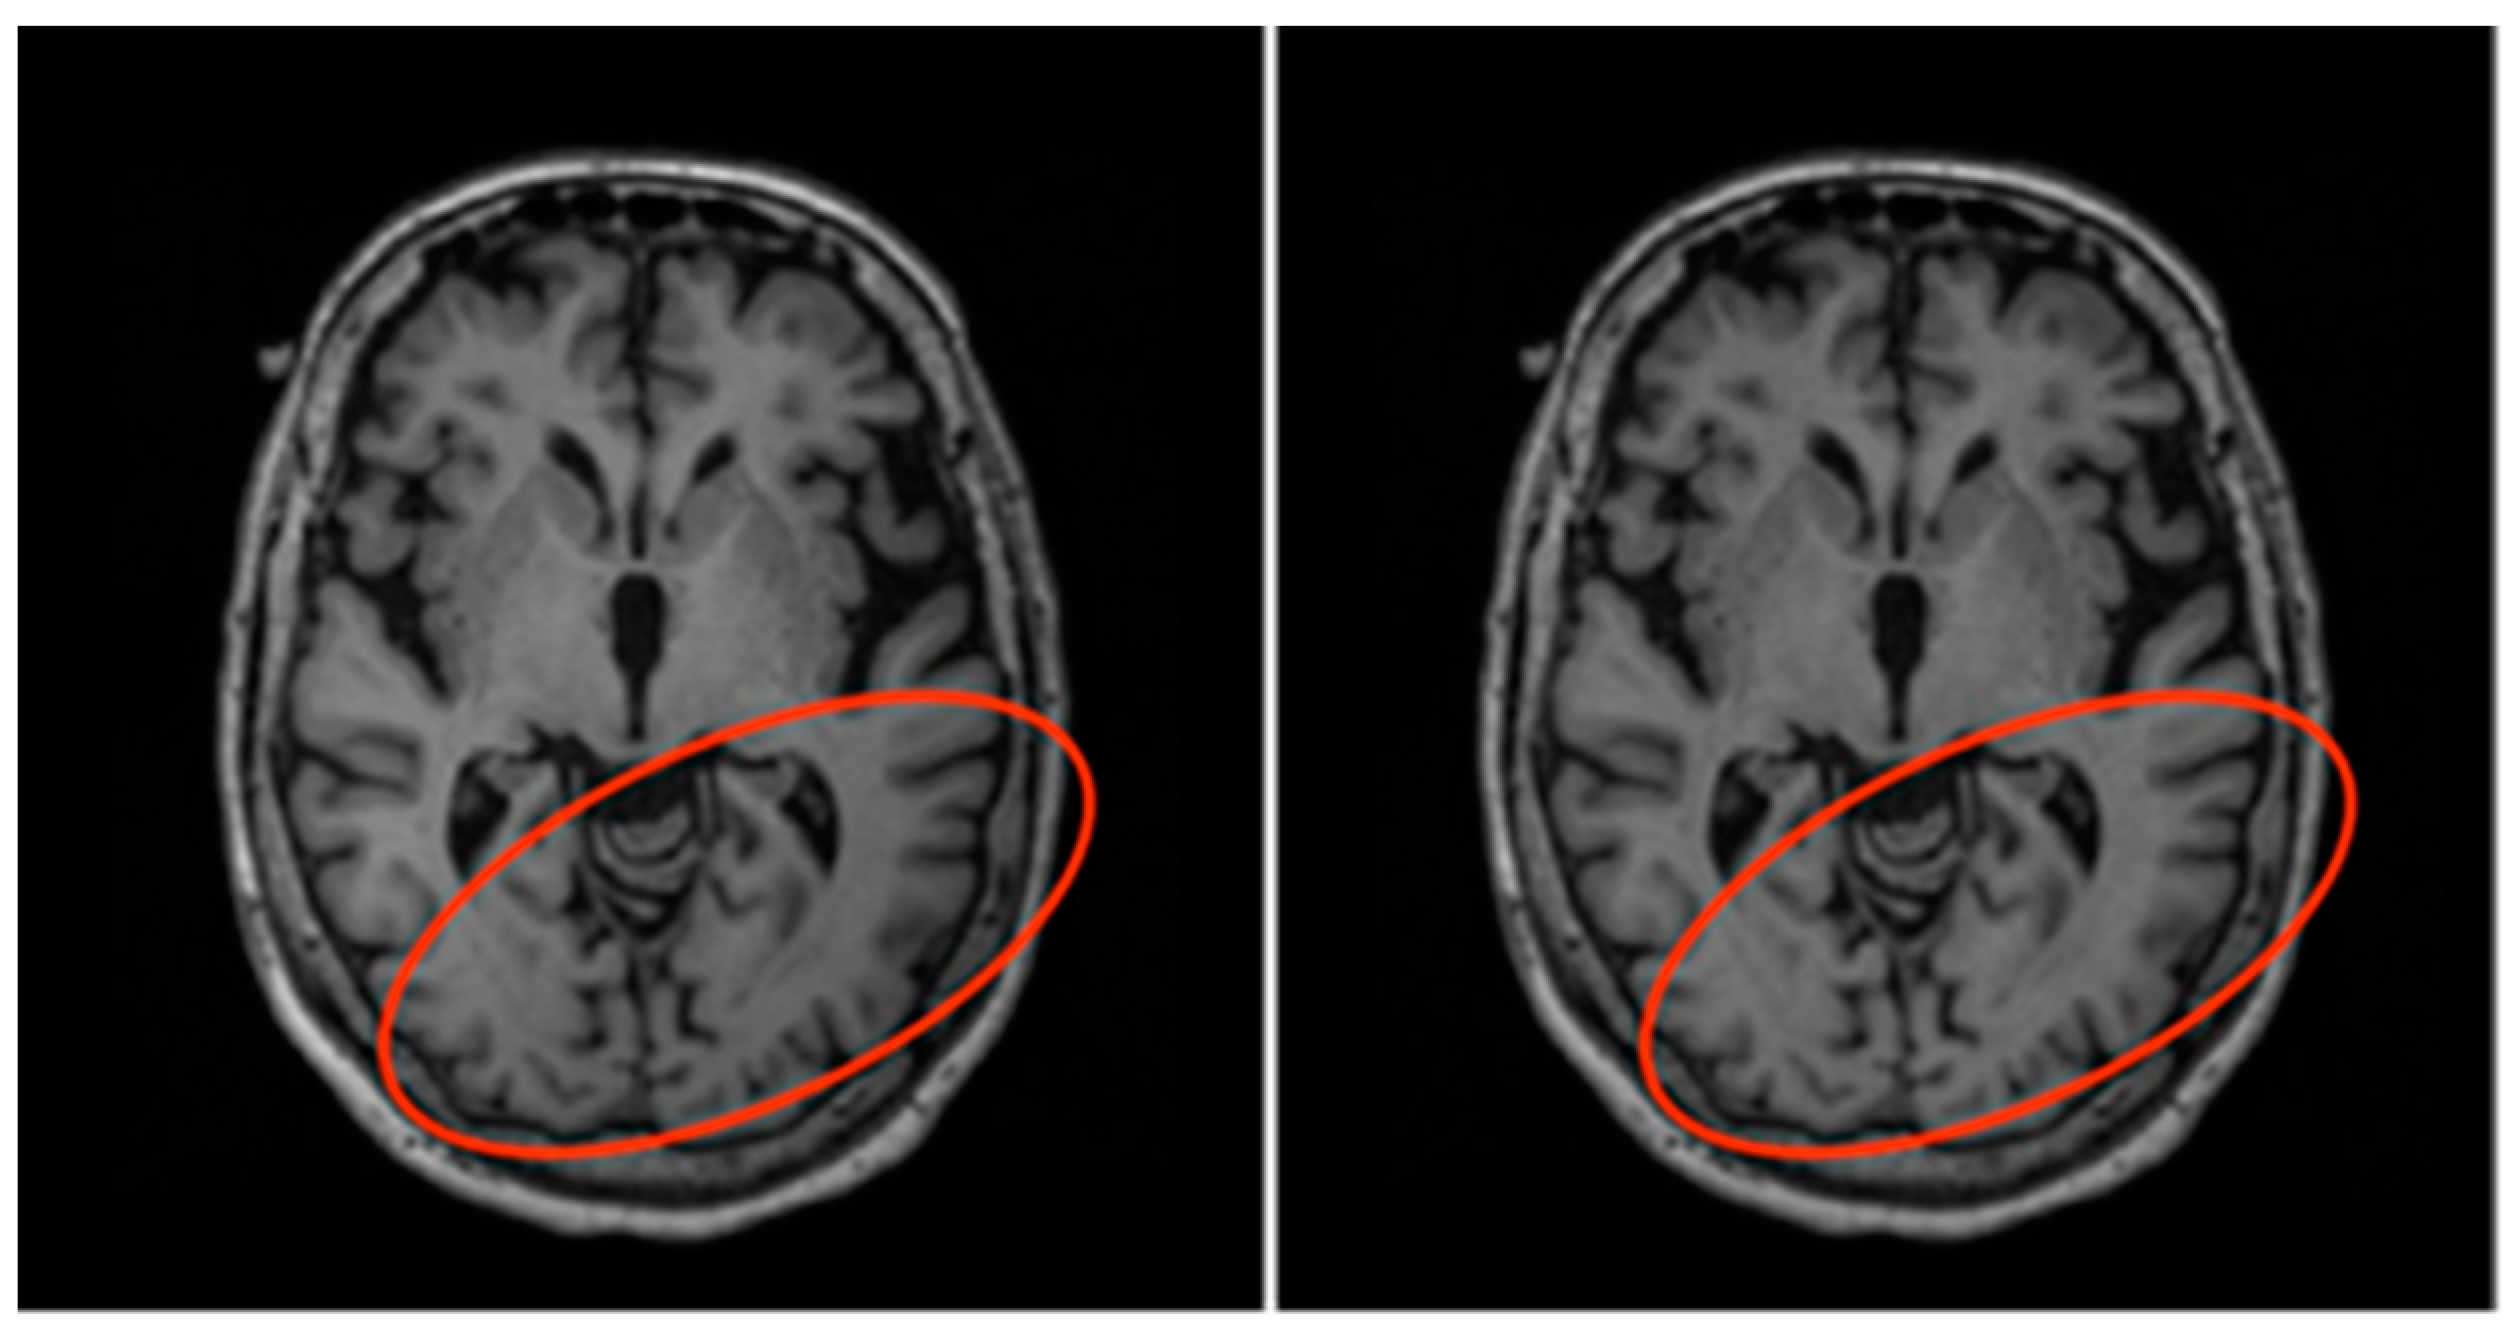

In order to ensure that majority of the brain MRI volumes were well aligned and properly registered, these 15 subjects and their volumes were removed from the dataset. Therefore, the final data consists of the MRI volumes and hippocampus masks of 115 subjects. The next step of pre-processing performed was field inhomogeneity correction, also known as bias field correction. During the acquisition of an MRI scan, the magnetic field weakens as it encounters brain tissue, thereby causing inconsistencies in the intensities through the volumes (even for the same tissue types) [37]. These inconsistencies can make it difficult for the models to accurately detect the boundaries of different tissue types. Therefore, the N4ITK algorithm was used to perform field inhomogeneity correction for all volumes in the dataset [41] as shown in Figure 6 below.

Figure 6.

Before (left) and after (right) N4ITK bias field correction. Notice the slight change in shade of the circled region.